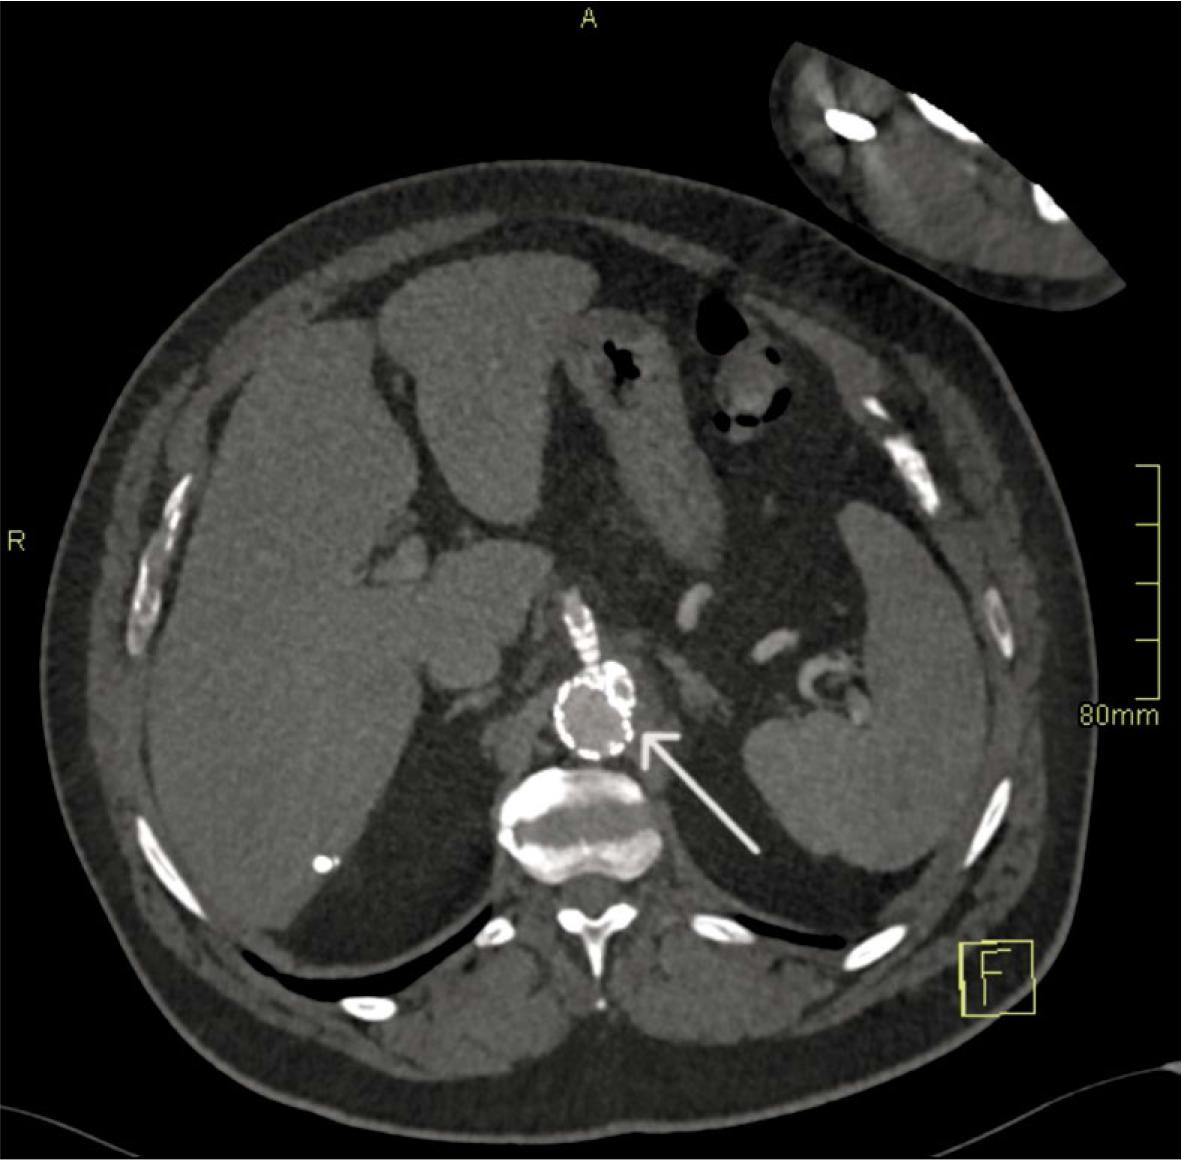

FIGURE 4.